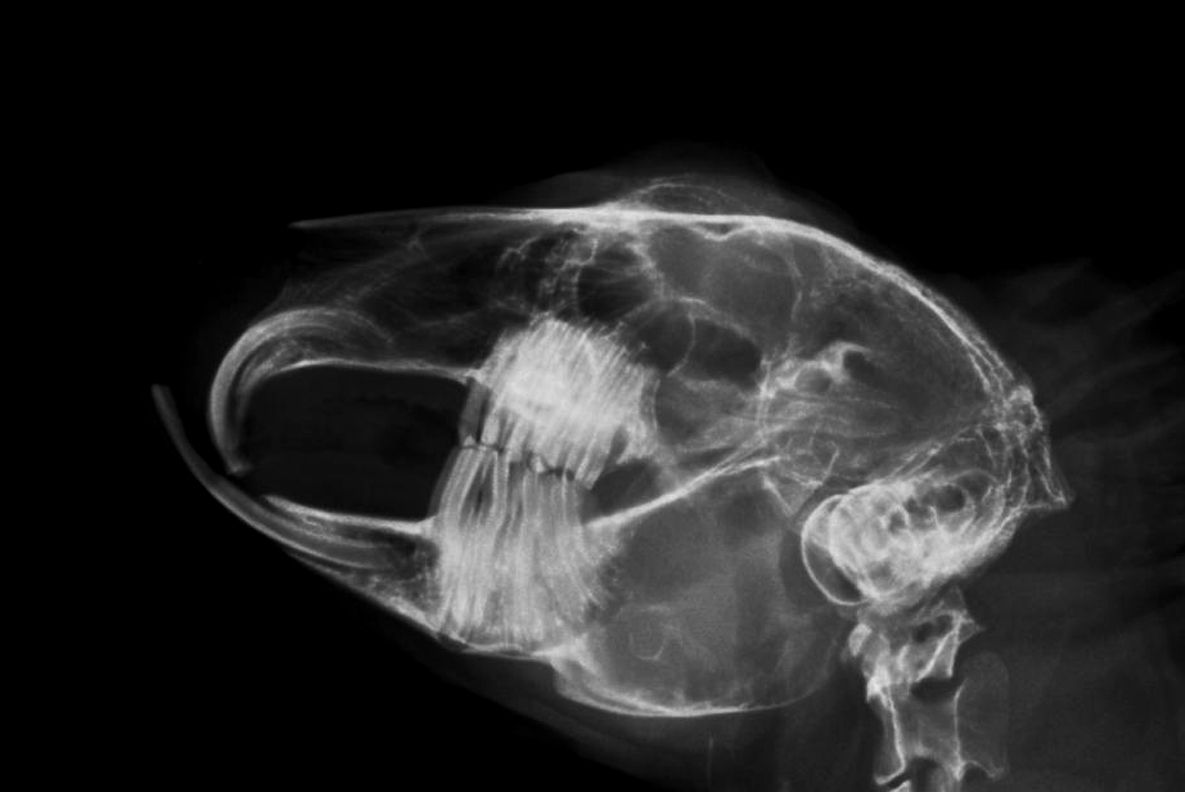

- Zahnheilkunde, Untersuchungen der Maulhöhle in Narkose in Verbindung mit bildgebender Diagnostik (Kopf-/Zahnröntgen), schonende und sichere Zahnkorrekturen mittels elektrisch betriebener Diamantschleifer